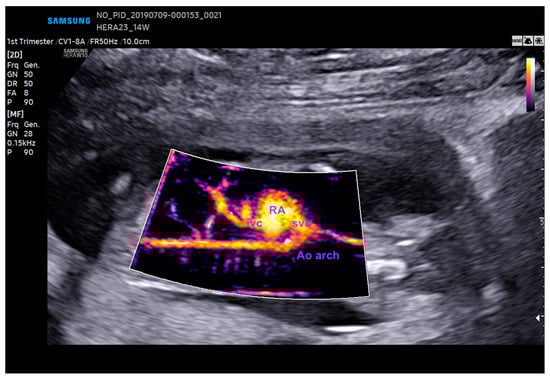

5. Realistic Vue, Crystal Vue, and LumiFlow

Realistic Vue, Crystal Vue, and LumiFlow (Samsung Healthcare, Gangwon, South Korea) provide more detailed and realistic images of the fetus with instant processing, and Crystal Vue improves the visualization of internal and external structures in a single rendered image (Figure 9 and Figure 10 and Video S6). LumiFlow is a post-processing and shading technique used to better assess the fetal micro- and macrovasculature of the fetus. This technology can be added to existing Doppler images, such as color/power, to simulate a 3D pace view of the fetal vasculature. With LumiFlow, the center of the vessel is displayed in a slightly lighter color due to its faster velocity, with a darker border around the vessels where blood velocities are slower (Figure 11) [38,39].

Figure 11.

The aortic arch as assessed by LumiFlow at 14 weeks gestation. RA: right atrium; Ao: aorta; svc: superior vena cava; ivc: inferior vena cava.